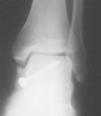

El seguimiento a la largo plazo de las fracturas del astrágalo identifica que la causa más común de los resultados pobres está asociada con la OA subastragalina, tibioastragalina y talonavicular, tanto en nuestra revisión, que alcanzó al 21% (8) de los casos (figs. 9 y 10), como en otros trabajos revisados15,17,19,22,23.

Fig. 9. --A) Fractura del cuerpo del astrágalo tipo B más rotura completa de los 3 ligamentos laterales del tobillo. B) Abordaje bilateral. Osteosíntesis. Sutura de ligamentos. Radiografía y tomografía computarizada a los 18 meses. Artrosis subastragalina y tibioastragalina.

Fig. 9. --a: Type B fracture of the astragalus with complete rupture of the 3 lateral ankle ligaments. b: Bilateral approach. Osteosynthesis. Ligament suture. Radiography and CT at 18 months. Sub-astragalar and tibio-astragalar arthrosis.

Fig.10. --Resultado a los 32 meses. 50° de BA. NAV del cuerpo y artrosis subastragalina y tibioastragalina

Fig.10. --Results at 32 months. BA 50º. Avascular necrosis of the astragalus and sub-astragalar and tibio-astragalar arthrosis.